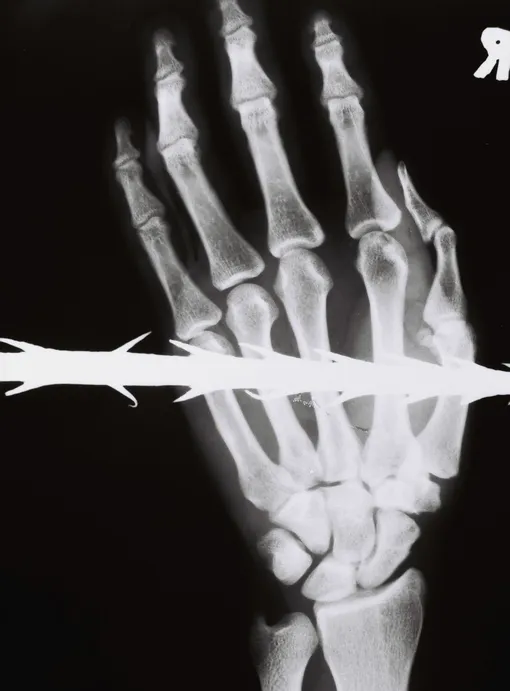

ЗИМБАБВЕ, 1997 ГОД

Копье с зазубринами пронзило ладонь молодого мужчины. Палач может использовать любой предмет, оказавшийся под рукой. Иногда тип этого предмета позволяет определить, в какой местности применялась пытка.